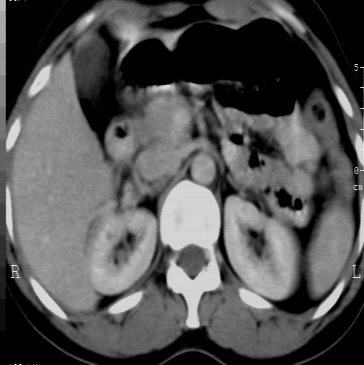

标题: CT24780:女 41岁 右肾多发低密度占位性病灶 [打印本页]

女 41岁 超声检查:右肾多发实质性包块,性质待查(提示:错构瘤或其它病变),临床病史不详。

右肾血管平滑肌脂肪瘤,双肾旋转不良。